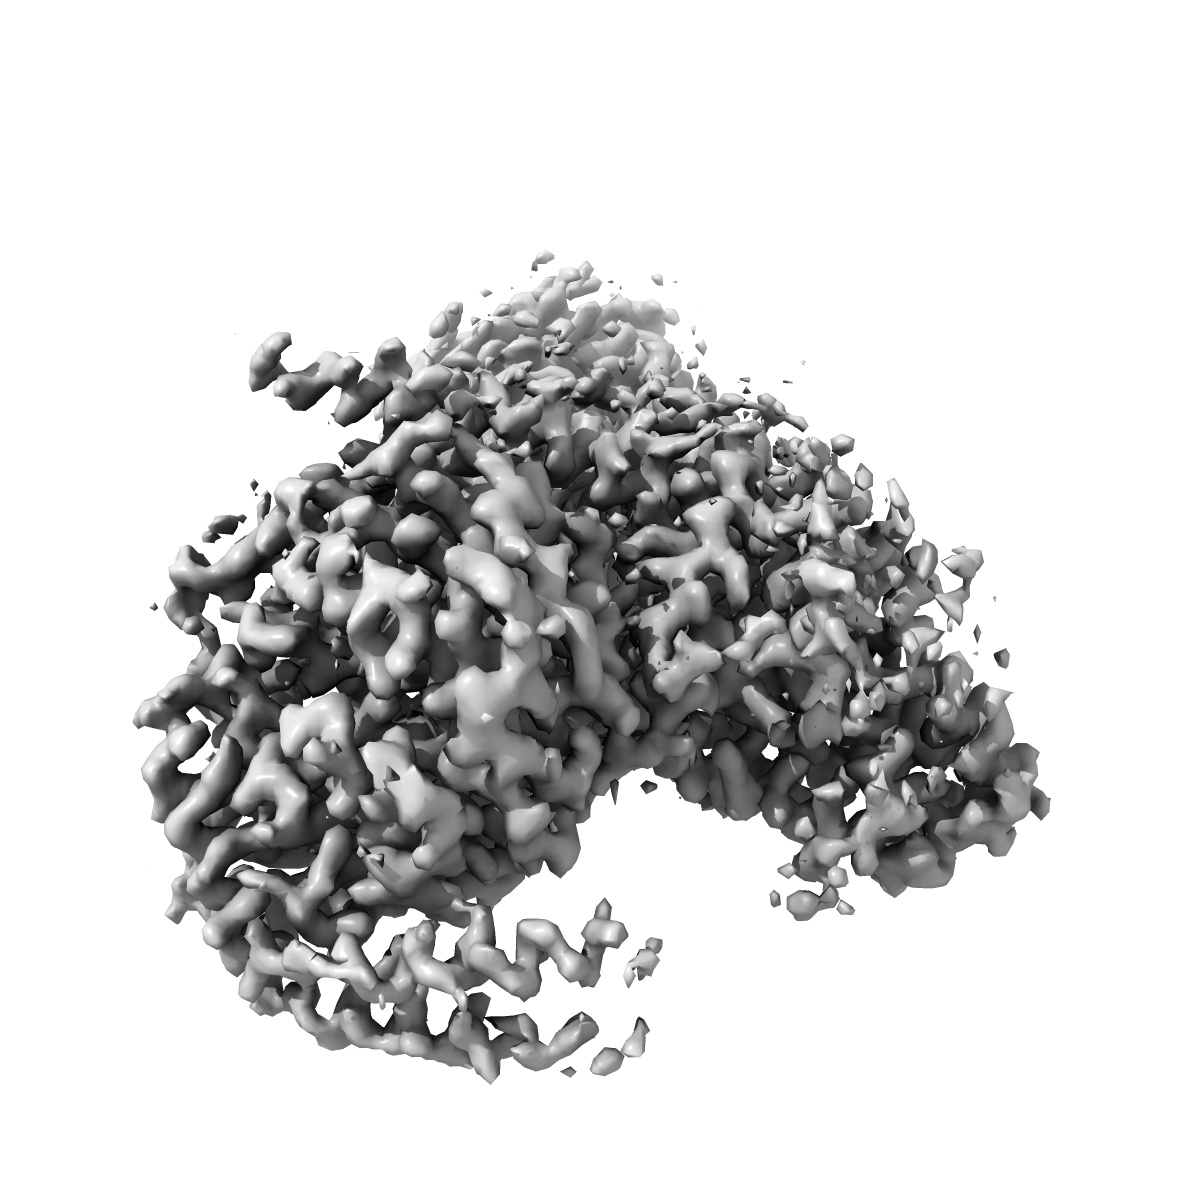

Cryo-EM structure of human angiotensin receptor AT1R in complex Gq proteins and Sar1-AngII

Single-particle2.9 Å

Sample: Angiotensin receptor AT1R in complex with Gq proteins and Sar1-AngII